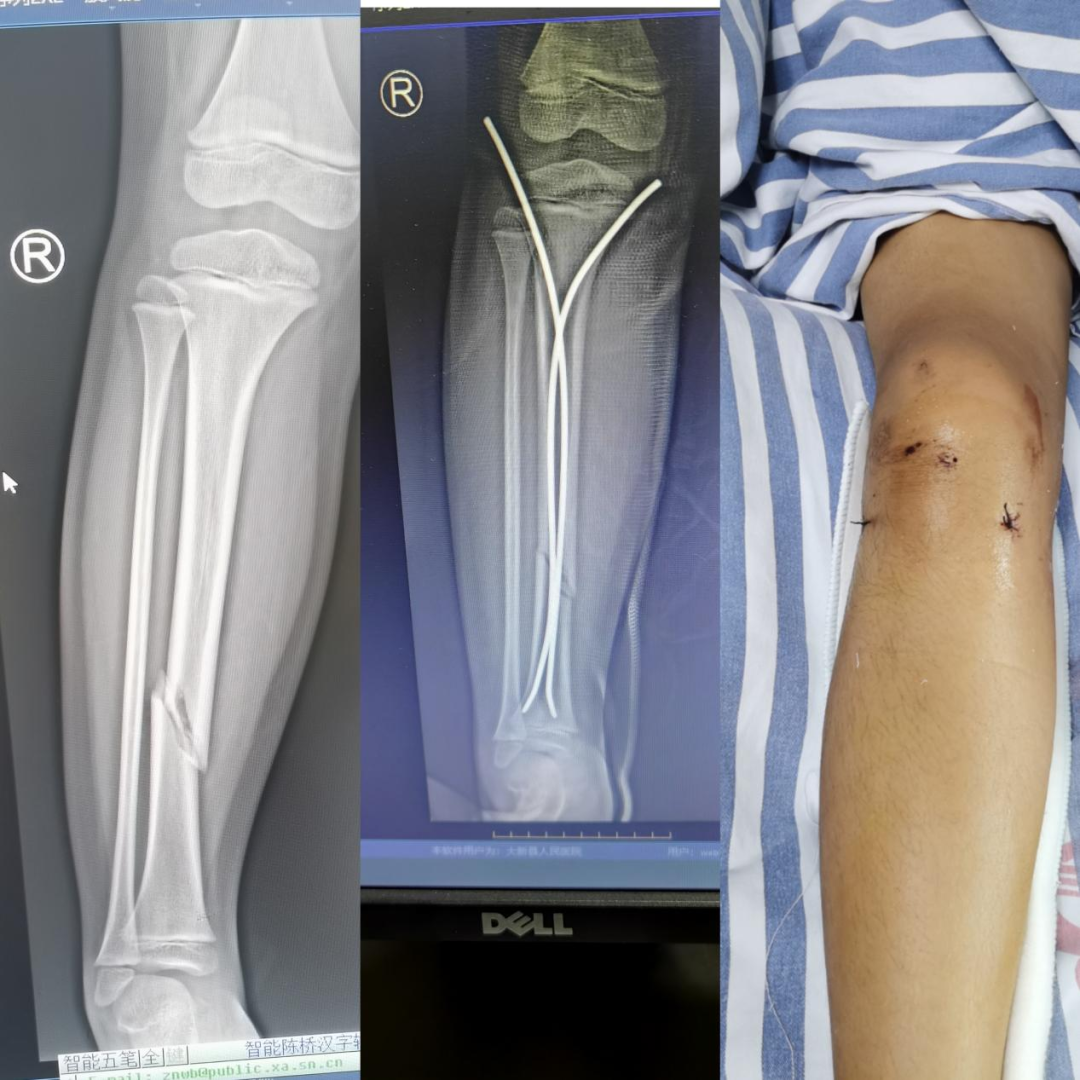

1. 年轻患者(尤其是儿童和青少年)

骨骼还在生长:对于儿童,内固定物可能影响骨骼的发育或生长板,通常需要择期取出。

活动周期长:年轻人未来数十年活动量大,内固定物长期留存可能增加远期疲劳断裂或影响周围组织的风险。